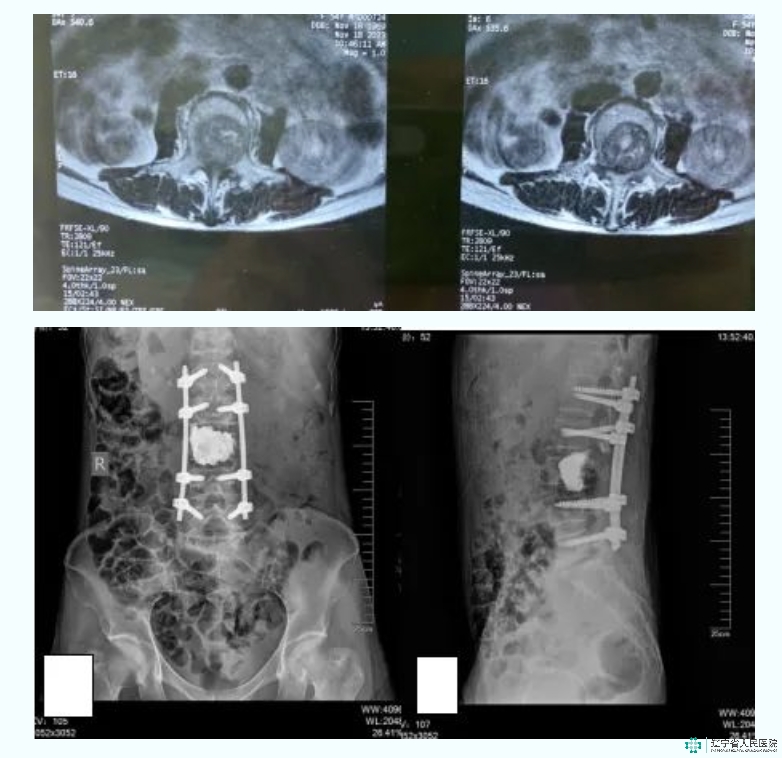

病例:高某某,女,58岁。诊断:腰3椎体转移瘤。Tomita评分:3分;SINS 评分:14分。采用分离手术腰3脊椎部分切除骨水泥占位内固定术。A-B-C:腰椎CT:矢状位、冠状位及轴位:可见腰3椎体溶骨性破坏;D-E:腰椎MRI矢状位及轴位:可见腰3椎体T2低信号改变,椎管内脊髓压迫显著,ESCC3级;F-G:腰椎正侧位DR:腰3椎体分离手术,术后改变。